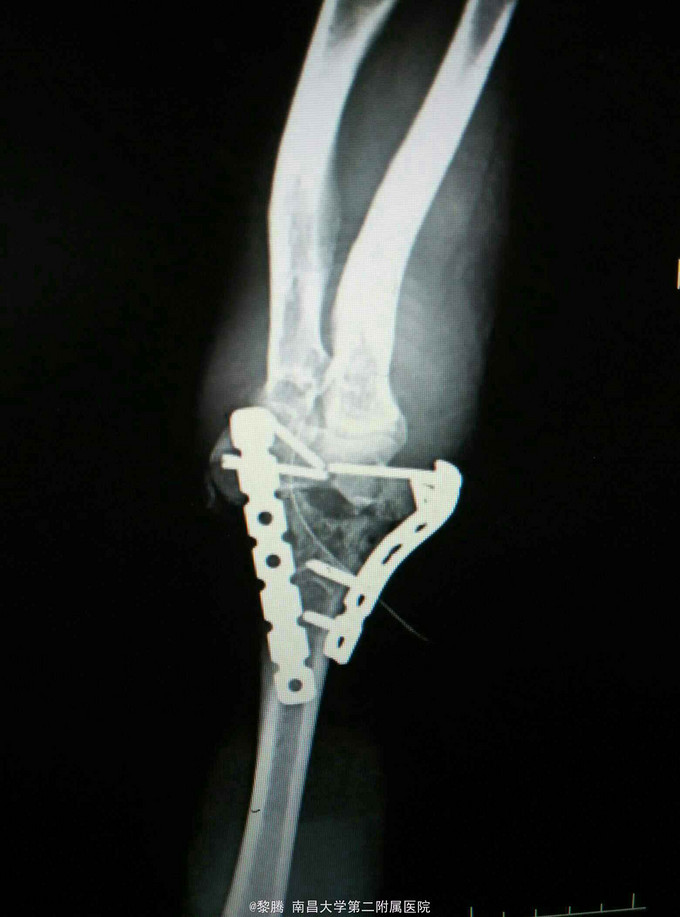

诊断:左肱骨髁间粉碎性骨折 治疗:骨折切开复位内固定+尺神经前置术

随访:患者术后4天出院,左肘关节伸屈活动较前明显好转。术后定期复查。 讨论:患者未予鹰嘴截骨入路亦有较好视野暴露,一般情况粉碎性肱骨髁间骨折,截骨能提供良好暴露,便于操作。患者术中应先找到尺神经并保护,随后进行后续操作。要注意术后功能锻炼,这样才有机会恢复肘关节活动度。